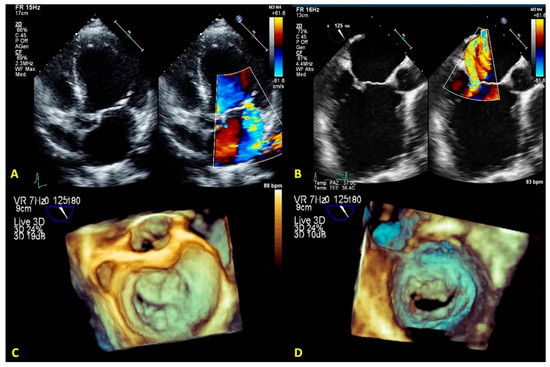

3.3. Quantification of Mitral Regurgitation

- The fourth step is the advancement of the Mitraclip in the LV. RT3DE with zoom modality in the L.A. or LV views represent direct visualization of the MitraClip concerning the MV and the line of coaptation, lowering the overall gain to get a clear impression of the clip in the LV views (Figure 20E).